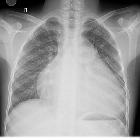

congenital heart defect

- congenital heart disease : CXR approach

- CXR approach to congenital heart disease

- chest x-ray appeoach to congenital heart disease

- congenital heart disease - chest x-ray approach